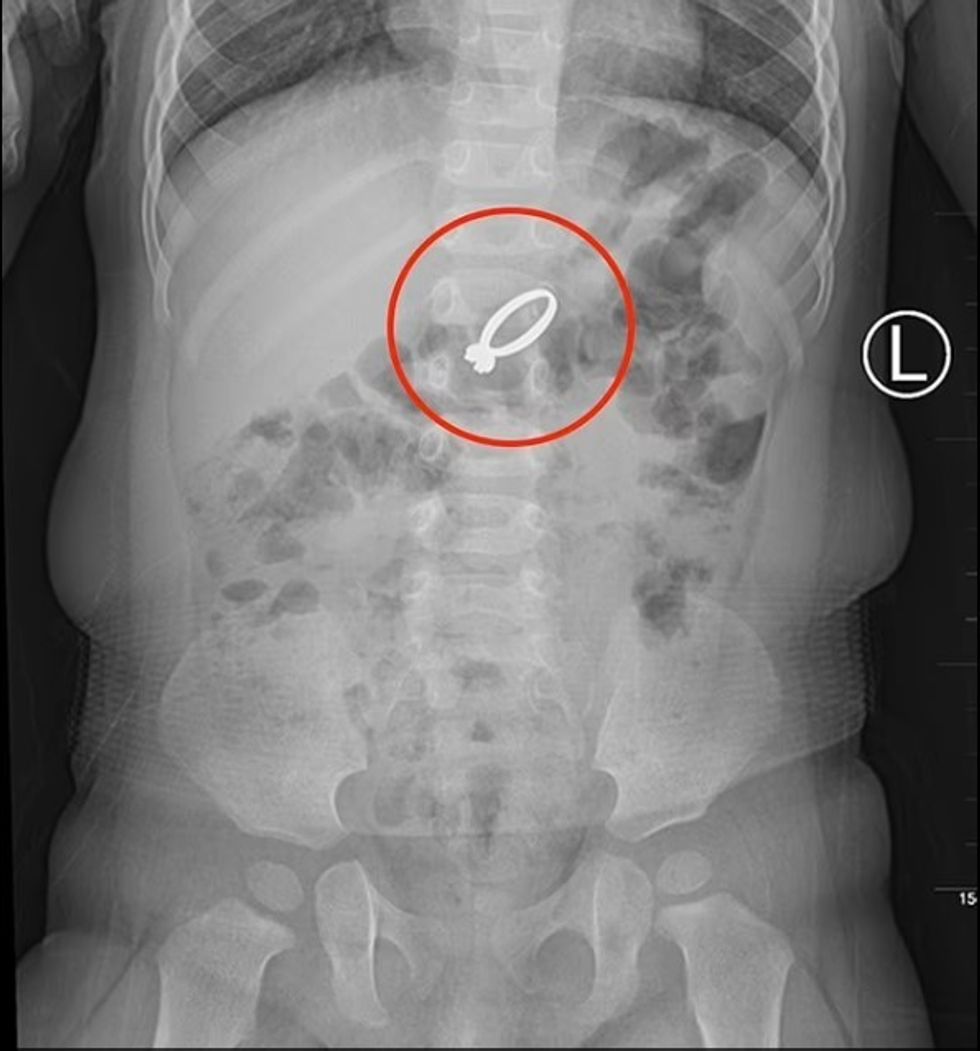

Kjo grua e dërgoi me urgjencë në spital të bijën 15-muajshe në Qingdao të Kinës, ku pas kryerjes së rëntgenografisë është zbuluar lokacioni i unazës së ëmës dhe arsyet pse vajza e saj kishte ankesa.

Unaza kishte përfunduar në barkun e vogëlushes, dhe për t’ia larguar mjekët u detyruan të kryejnë një ndërhyrje kirurgjike.